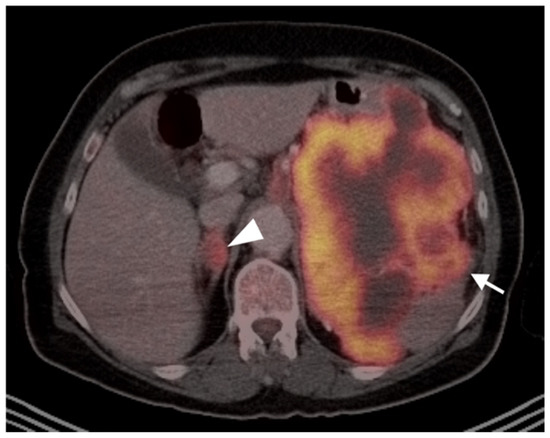

3.1.6. Liposarcoma

- Gao, Y.-J.; Yang, Z.; Yu, J.-Y.; Li, N.; Wang, X.-J.; Zhou, N.-N. Potential application value of PET/computed tomography in retroperitoneal leiomyosarcoma and a literature review. Nucl. Med. Commun. 2021, 42, 800–810. [Google Scholar] [CrossRef]

- Subramaniam, S.; Callahan, J.; Bressel, M.; Hofman, M.S.; Mitchell, C.; Hendry, S.; Vissers, F.L.; Van der Hiel, B.; Patel, D.; Van Houdt, W.J.; et al. The role of 18 F-FDG PET/CT in retroperitoneal sarcomas—A multicenter retrospective study. J. Surg. Oncol. 2021, 123, 1081–1087. [Google Scholar] [CrossRef]